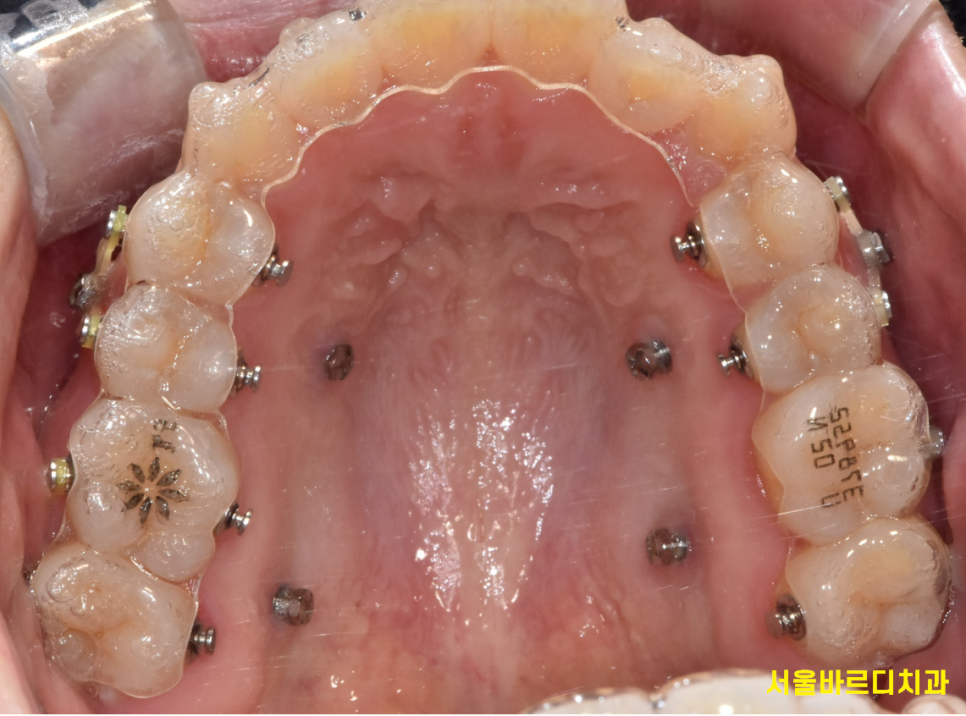

치아교정 장치는 크게 고정식 교정 장치와 가철식 교정 장치로 나눌 수 있습니다.

250304 철사형 장치

철사를 붙여서 진행할지~

꼈다 뺐다하는 투명교정으로 진행할지 결정해주어야하는거죠